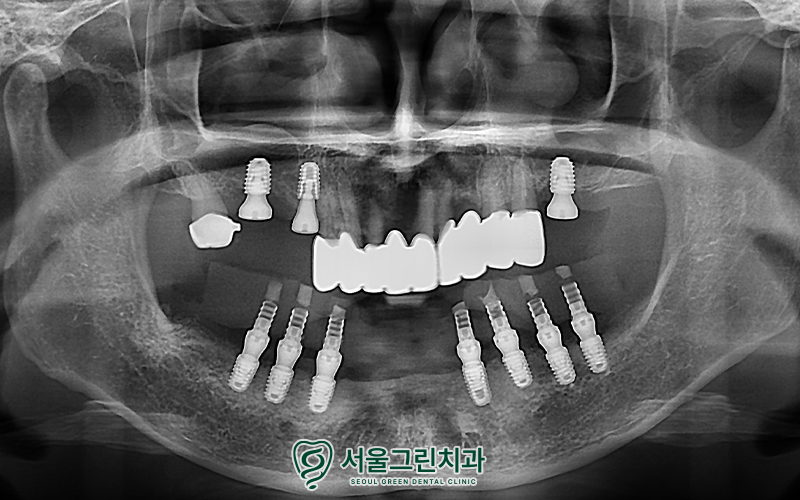

틀니 탈착의 번거로움 및 저작력 향상을 위해

임플란트 식립을 기본으로

치료 계획을 수립하였는데요.

✅ 아래쪽(하악)

.

ㅡ> 전체 임플란트의 경우

비용이 부담 되기에

비용 부담은 낮추면서

전체 임플란트의 기능 대비 효과가 좋은

‘올온엑스’ 진행

✅ 위쪽(상악)

ㅡ> 살릴 수 있는 치아는

가능한 살려 브릿지 제작 후,

소량의 임플란트 식립으로

치아 기능 회복시키기로 함

계획한 위치 및 방향대로

아래쪽 임플란트를 먼저 진행하였고,

위쪽도 순차적으로

치료를 진행했습니다.